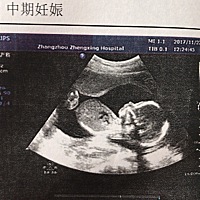

好可爱,有人能看出男女吗